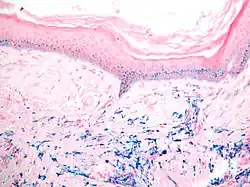

Histologie eines Hautbioptates bei Pseudozyanose: Ablagerungen eisenhaltigen Pigmentes in Dermis und basalen Epidermislagen (Berliner-Blau-Reaktion).

Auch das häufig in der Akne-Therapie eingesetzte Antibiotikum Minocyclin aus der Gruppe der Tetracycline kann bei längerfristiger Anwendung zu einer abnormen Pigmentierung führen. Im Bereich der Haut werden drei Formen unterschieden. Beim Typ I kommt es zu einer blauschwarzen oder grauen Pigmentierung des Gesichts, speziell in Arealen, in denen eine Akne-bedingte Vernarbung oder Entzündung vorliegt. Typ II manifestiert sich an der Haut von Schienbeinen oder Unterarmen als blau-graue Pigmentierung. Eine diffuse schmutzig-braune Verfärbung in sonnenexponierten Arealen wird beim Typ III beobachtet. Das extrazellulär in der Dermis und in dermalen Makrophagen abgelagerte Pigment der Typen I und II zeigt eine Positivität im histochemischen Eisennachweis (Berliner-Blau-Färbung), erweist sich immunhistochemisch aber auch als Melanin-positiv. Beim Typ III zeigt sich eine Melanin-positive Pigmentierung in basalen Keratinozyten sowie in dermalen Makrophagen. Die pathobiochemischen Ursachen der Pigmentierung sind unbekannt, möglicherweise spielen polymerisierte Metabolite oder unlösliche Chelationsprodukte des Medikaments eine Rolle. Die Pigmentierung bei den Typen I und II sind rückbildungsfähig, beim Typ III irreversibel.[4]